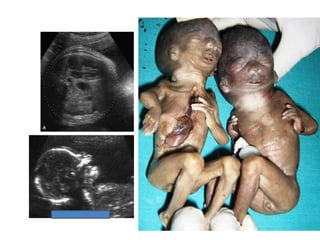

Amniotic band sequence:

Amniotic band sequence refers to a highly variable

spectrum of congenital anomalies that occur in

association with amniotic bands

Amniotic band sequence: Amnioticband sequence refers to a highly variable spectrum of congenital anomalies that occur in association with amniotic bands The estimated incidence of ABS ranges from 1:1200 to 1:15,000 in live births, and 1:70 in stillbirths

Anomalies include: Craniofacial abnormalities— eg, encephalocele, exencephaly, clefts, which are often in unusual locations; anencephaly. Body wall defects (especially if not in the midline), abdominal or thoracic contents may herniate through a body wall defect and into the amniotic cavity. Limb defects — constriction rings, amputation, syndactyly, clubfoot, hand deformities, lymphedema distal to a constriction ring. Visceral defects — eg, lung hypoplasia. Other — Autotransplanted tissue on skin tags, spinal defects, scoliosis, ambiguous genitalia, short umbilical cord due to restricted motion of the fetus